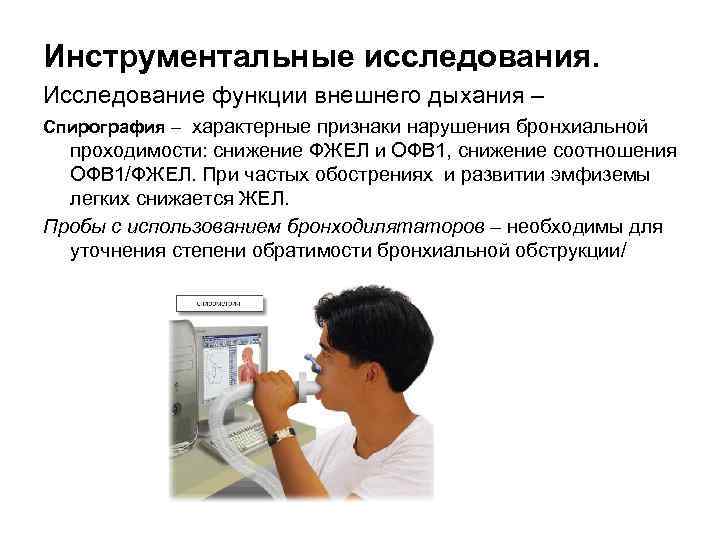

Инструментальные исследования. Исследование функции внешнего дыхания – Спирография – характерные признаки нарушения бронхиальной проходимости: снижение ФЖЕЛ и ОФВ 1, снижение соотношения ОФВ 1/ФЖЕЛ. При частых обострениях и развитии эмфиземы легких снижается ЖЕЛ. Пробы с использованием бронходилятаторов – необходимы для уточнения степени обратимости бронхиальной обструкции/